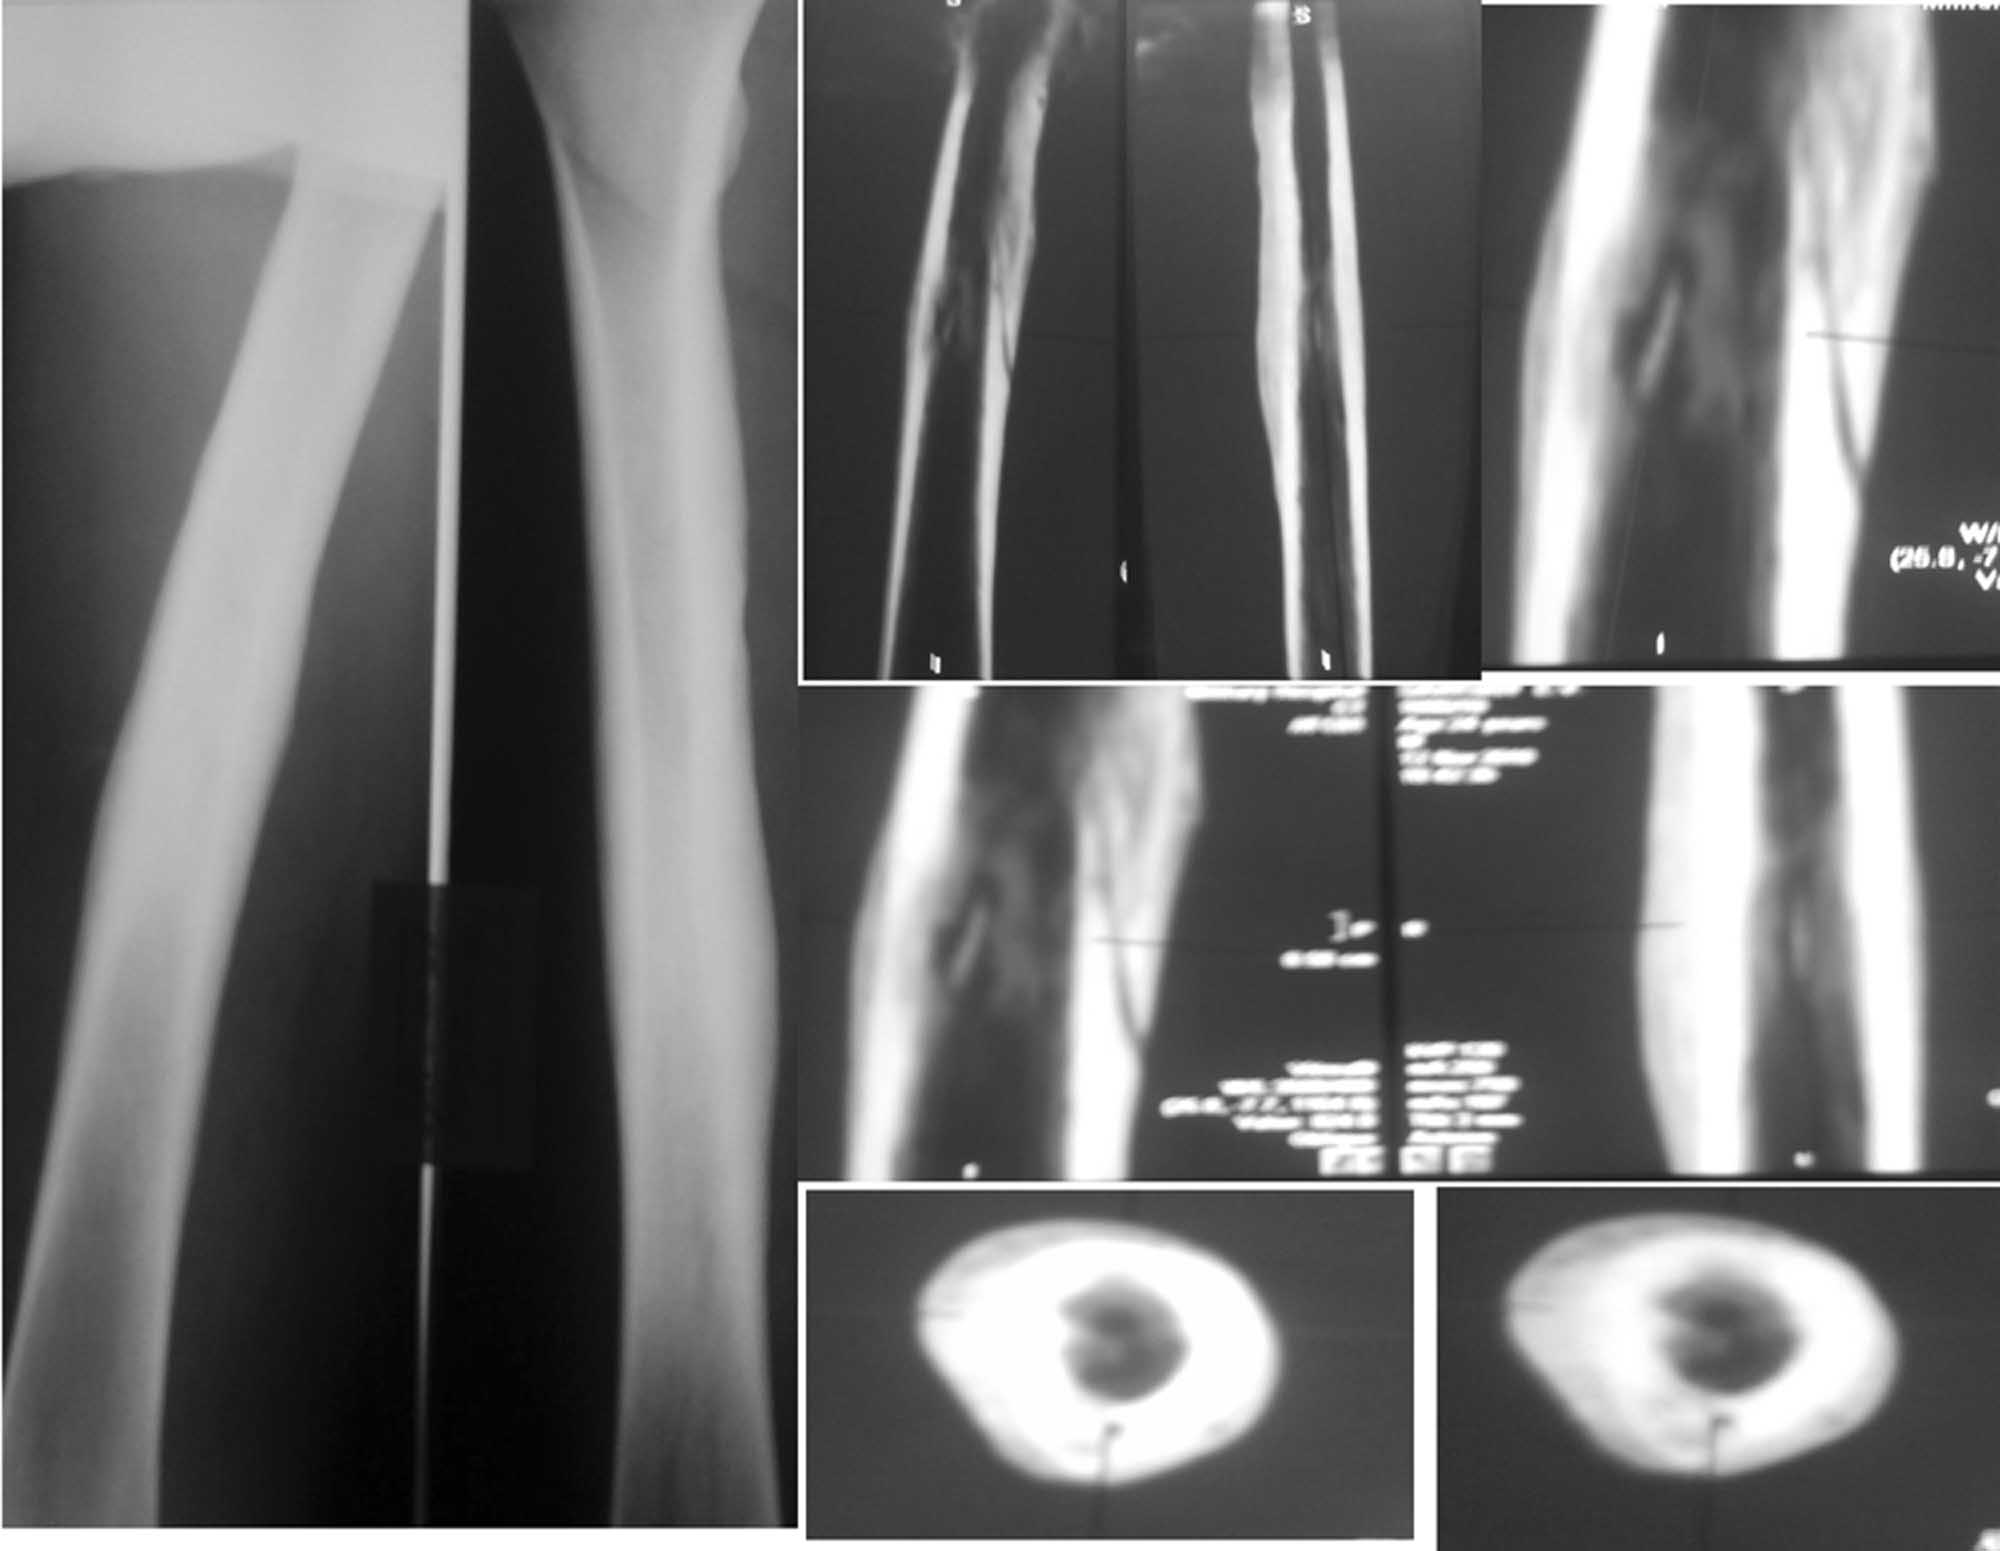

Случай «вялотекущего» гематогенного остеомиелита у молодого пациента

Пациенту 24 года. Беспокоят умеренные боли в области нижней трети правого бедра при нагрузках и ограничение сгибания правого коленного сустава. В покое, в т.ч. ночью, болей нет.

2 года назад без видимой причины появились боли и припухлость в нижней трети правого бедра. Был госпитализирован в отделение гнойной хирургии с диагнозом «Воспалительный инфильтрат». Рентгенограммы бедра в тот период патологии не выявили. На фоне а/б терапии цефазолином инфильтрат разрешился полностью.

Последующие 2 года ничего не беспокоило. Около 2 недель назад появились боли и припухлость в нижней трети правого бедра, вновь без видимой причины. На рентгенограммах бедра выявлены выраженная периостальная реакция, на КТ признаки хронического гематогенного остеомиелита.

Объективно: внешне мягкие ткани бедра не изменены, следов от свищей нет, умеренно болезненна область нижней трети правого бедра по медиальной поверхности, без изменения кожной температуры, признаков инфильтрации и флюктуации. Ограничено сгибание в правом коленном суставе до 90 гр из-за болей.

Лабораторные данные без особенностей за исключением СОЭ – 25 мм в час, уровень СRP в 2 раза выше нормы.

Моё мнение, что это хронический(гематогенный) остеомиелит правого бедра в ср. трети, секвестральная, безсвищевая форма. возможно происходит формирование ещё и секвестра наружного кортикала.